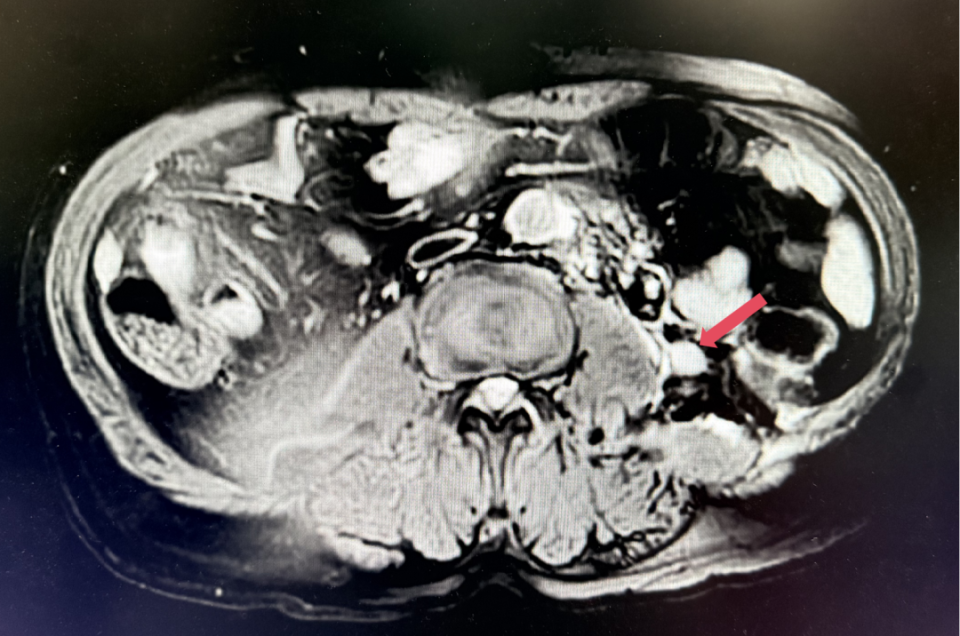

2023年3月:用药6周(C2)后首次肿评,肿瘤负荷减少至76.8mm,达到PR。

2023年3月,初始应答